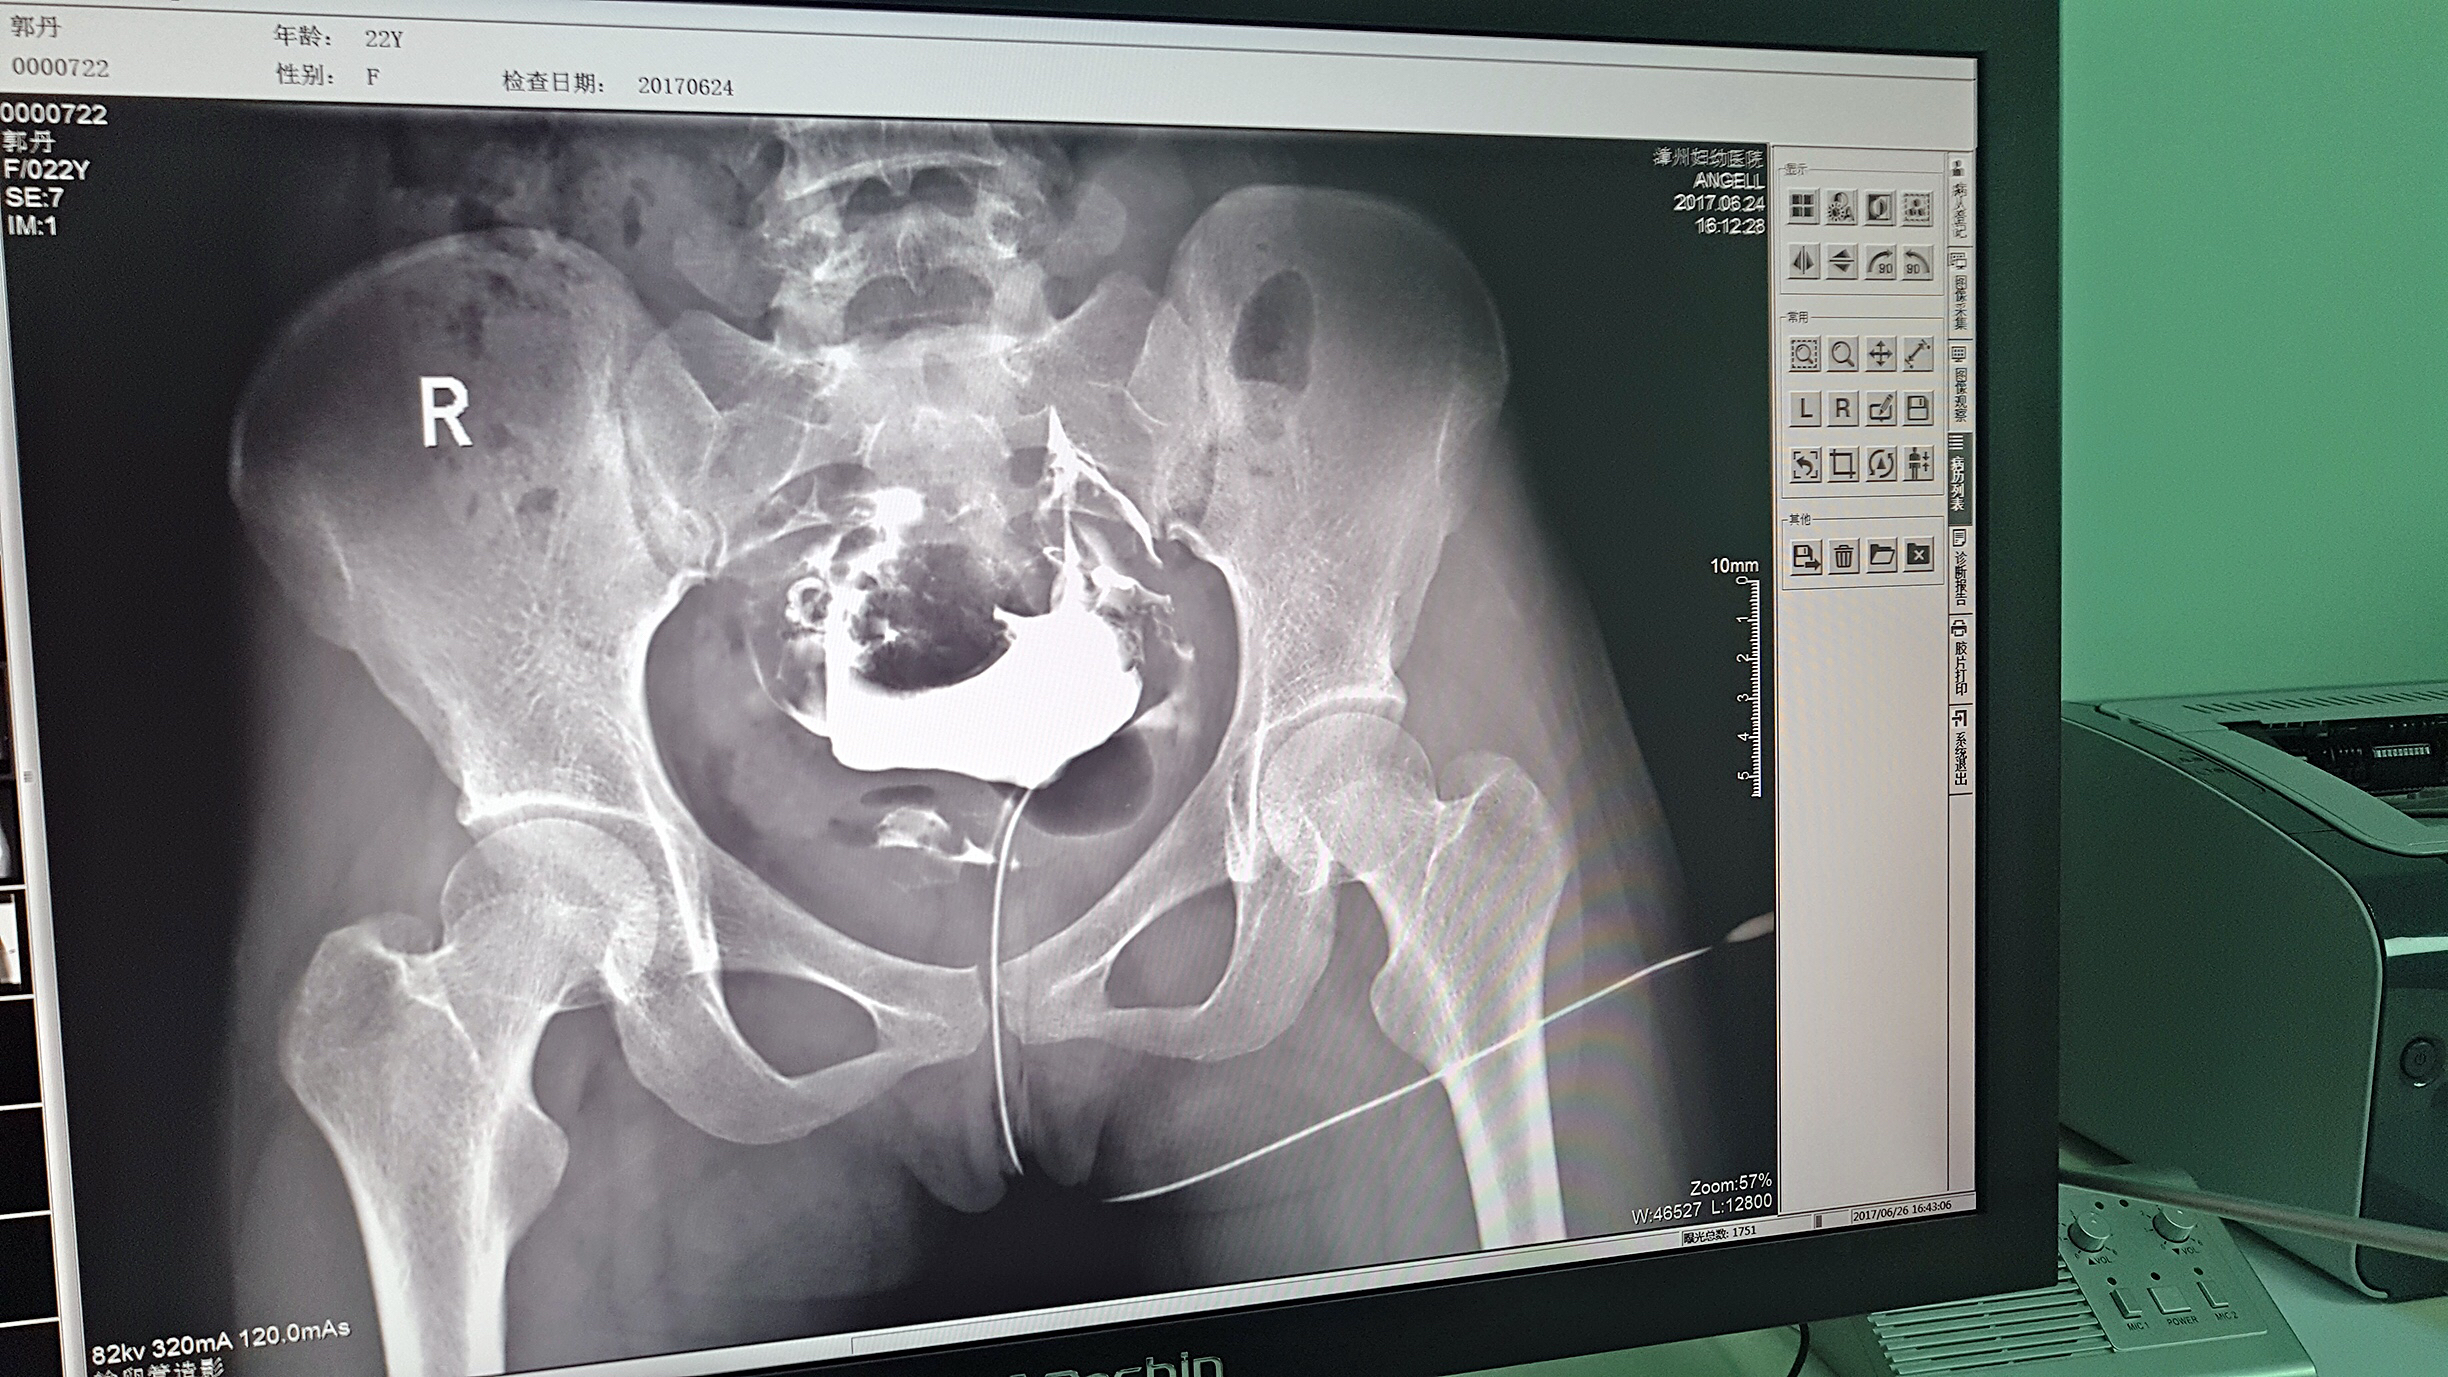

目前設備除了用于常規拍片之外,主要用于輸卵管造影檢查,平均每個月有超過20個患者在漳州婦幼醫院做輸卵管造影檢查。在此之前,漳州市只有市醫院、175解放軍區醫院等大三甲醫院才能做輸卵管造影檢查,這不僅讓三甲醫院人滿為患,而且下級醫院卻因為不能做某項檢查而造成資源浪費。因為有了設備,漳州婦幼醫院可以滿足患者的一些特殊檢查需求,已經有很多患者慕名而來。

漳州婦幼醫院放射科的陳主任日常跟這臺設備打交道是最多的,他最有發言權。在安健科技的回訪中,陳主任說:這臺設備具備先進的診斷功能,操作方便,能夠拍攝出清晰的影片,進而對患者病情能夠實現精準診斷。同時在醫院對患者診斷能力方面有較大提升,留住了大量患者,為患者提供了更好的醫療服務。